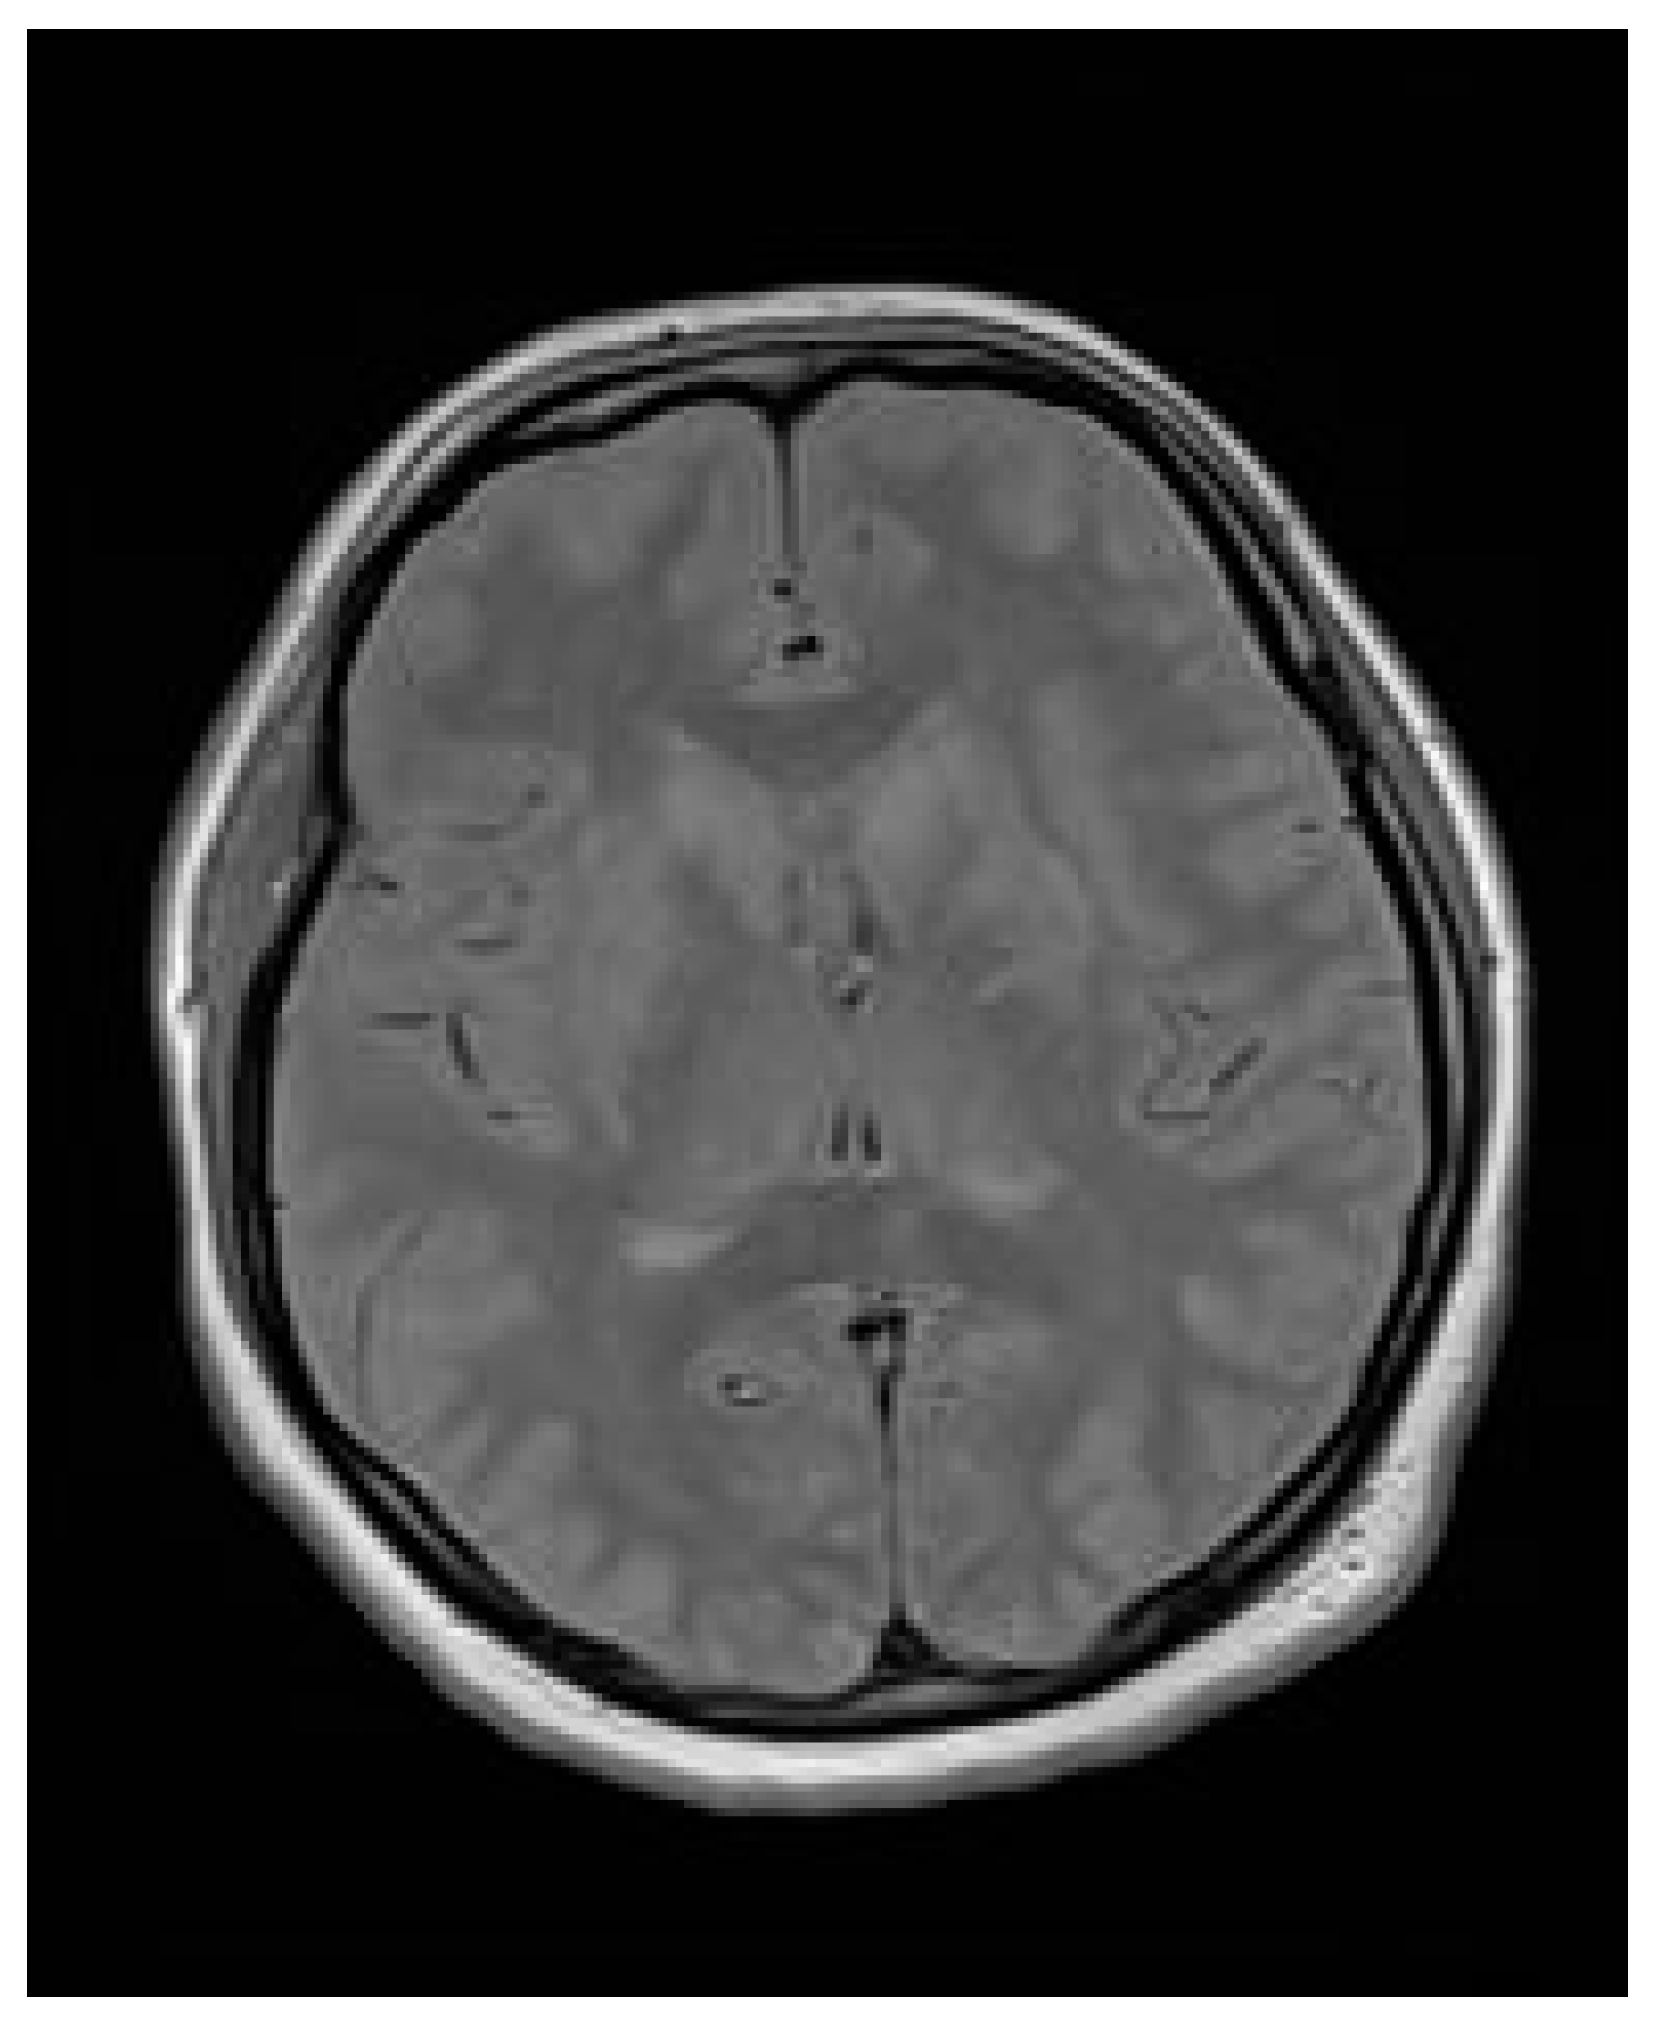

Due to the serious general condition of the patient, she was transferred to the department of anesthesiology and intensive care for the treatment of acute respiratory failure and complications of hypertensive encephalopathy. A control brain MR at post-cesarean day 3 and day 7 (Figure 4) described a remission in changes in the course of PRES—a condition in which parts of the brain are affected by swelling—and a reduction in cerebral edema, which ultimately allowed for discontinuation of analgesia, sedation and extubation of the trachea on post-cesarean day 7. During hospitalization in the ICU, hematological diagnostics were performed, and the presence of circulating anticoagulants was excluded.

The discharge recommendations included outpatient OB/GYN, hypertension, neurological and psychiatric appointments and further psychological care. The pharmacotherapy prescribed included nitrendipine, beta-blockers, levetiracetam, sertraline and estazolam at night in the case of insomnia. The patient remained in the outpatient care of the tertiary hospital, and at a gynecological follow-up visit performed 3 months after the cesarean section, a transvaginal ultrasound revealed correct healing of the uterus (Figure 5). The patient sustained no long-term mental or neurological impairments, yet she remains under yearly observation. Due to normalization in her blood pressure, hypotensive treatment was stopped, and the patient was scheduled for yearly echocardiography and ophthalmological scans.

Figure 4. Brain MR performed after 7 days of treatment at the intensive care unit with remission in changes in the course of PRES and a reduction in cerebral edema.

Figure 5. Transvaginal ultrasound revealed correct uterus healing 3 months after the cesarean section.